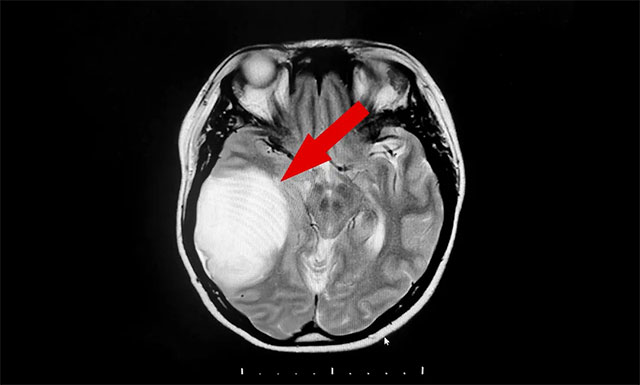

由于當(dāng)?shù)蒯t(yī)療條件所限,患者遂在親友推薦下慕名來到上海藍(lán)十字腦科醫(yī)院尋求進(jìn)一步診斷治療。入院后,經(jīng)頭顱增強(qiáng)核磁檢查,發(fā)現(xiàn)患者右側(cè)顳葉單發(fā)巨大混雜信號(hào)占位病變,病灶約 5.4×6.7×4.9 cm,結(jié)合病灶影像特點(diǎn),診斷其為膠質(zhì)瘤可能性較大。

▲ 患者右側(cè)顳葉單發(fā)巨大混雜信號(hào)占位病變